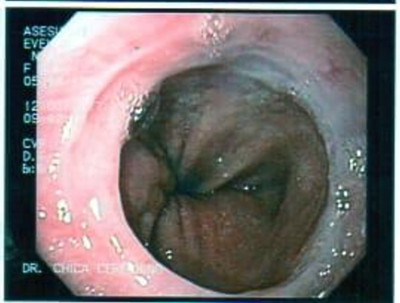

Paciente con várices esofágicas

Post Image